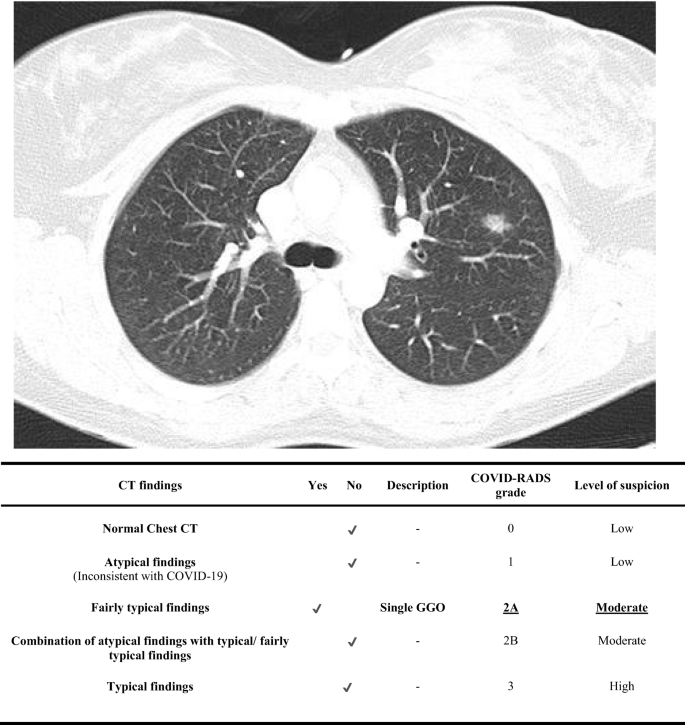

Coronavirus Disease 2019 Covid 19 Imaging Reporting And Data System Covid Rads And Common Lexicon A Proposal Based On The Imaging Data Of 37 Studies Springerlink